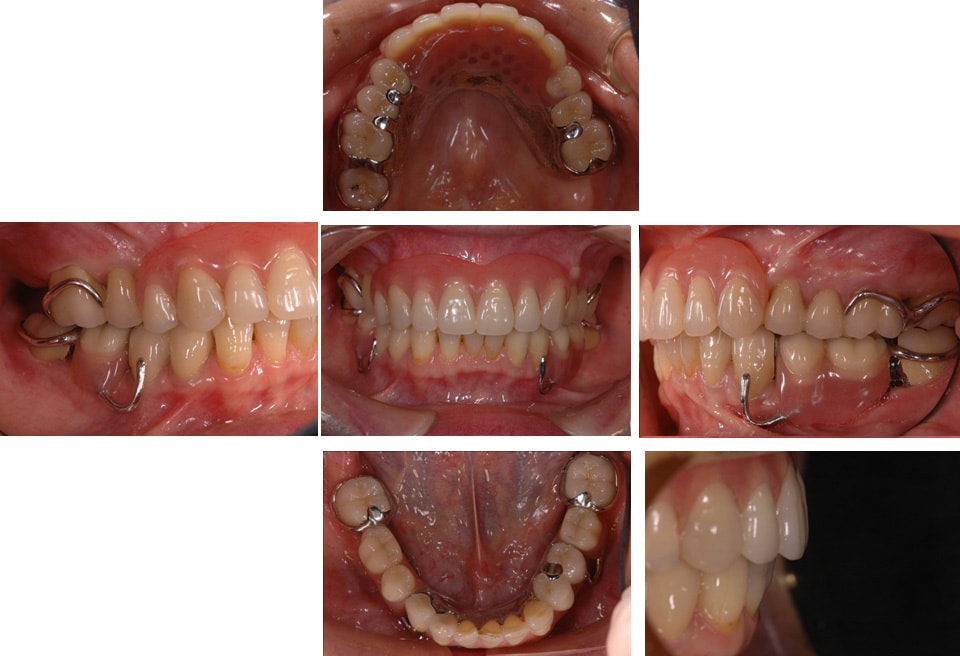

部分矯正を含めた全顎的な治療

前歯の治療前後

右奥歯の治療前後

左奥歯の治療前後

上の歯の治療前後

下の歯の治療前後

最小限の矯正治療や過去に治療した銀歯の隙間から虫歯になった歯や神経の再治療を行いました。もう少し修正が必要なのですが、部分矯正も含め長い治療になり、とりあえずはお疲れさまでした。

治療は、僕たちは当然ですが、患者さんにも頑張って頂いて初めてうまくいくものかなとも思います。定期的に通院していただいたり、治療が間延びしないことも治療がうまくいく要因の一つのように感じます。

治療が終了して終わりではなく、維持するためこれからメンテナンスが、始まると思っていただければ幸いです。現状が、できるだけ長期に維持できればと考えています。